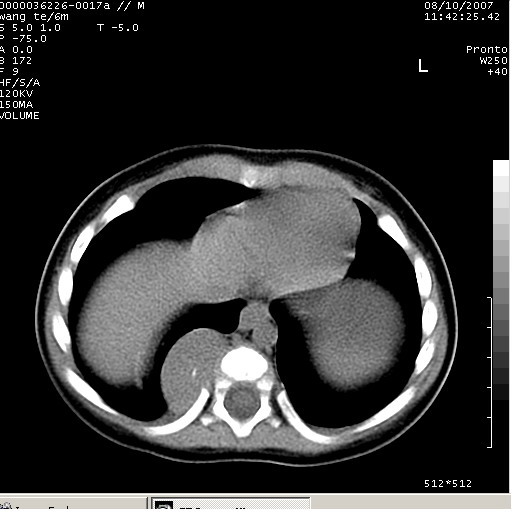

患儿男、6个月,因咳嗽三天曾拍胸片考虑肺部感染,这是在胸片后约一周左右作的ct。

右下肺纵隔旁软组织密度影,宽基底紧贴胸椎与肋骨,边界清楚,内见点状高密度影。支持考虑:神经源性肿瘤!肺隔离症待排

图有点少,但能看出越往下似乎越大,我认为除了考虑神经源性肿瘤,还要考虑膈疝可能

同意神经源性肿瘤的诊断,如果患儿一般情况不差的话,神经节细胞瘤可能性要大一些,隔离肺的可能性小,如果考虑叶内型隔离肺,孩子平时感染的机会可能比较多,增强后可排除